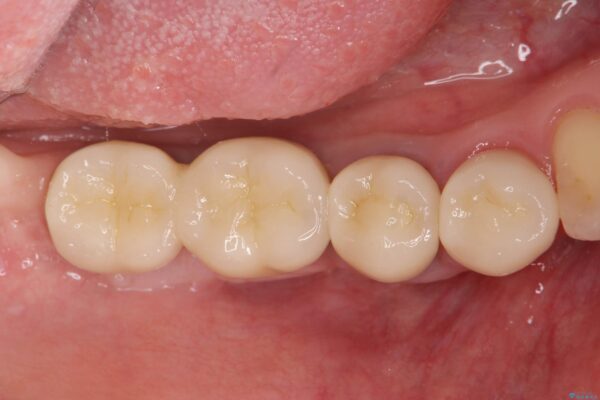

治療後

遊離歯肉移植術を伴うインプラント治療 治療後画像 遊離歯肉移植術を伴うインプラント治療 治療後画像 遊離歯肉移植術を伴うインプラント治療 治療後画像 遊離歯肉移植術を伴うインプラント治療 治療後画像